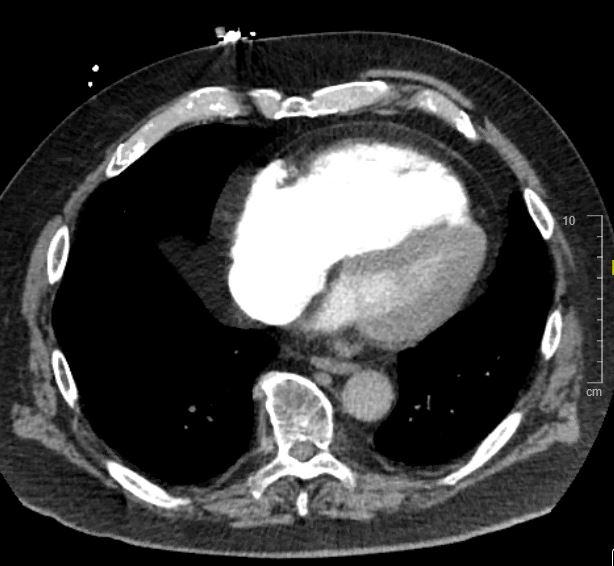

CT chest:

CT chest interpretation: saddle pulmonary embolism

CT chest: Evidence of RV strain. Note RV is larger than LV.